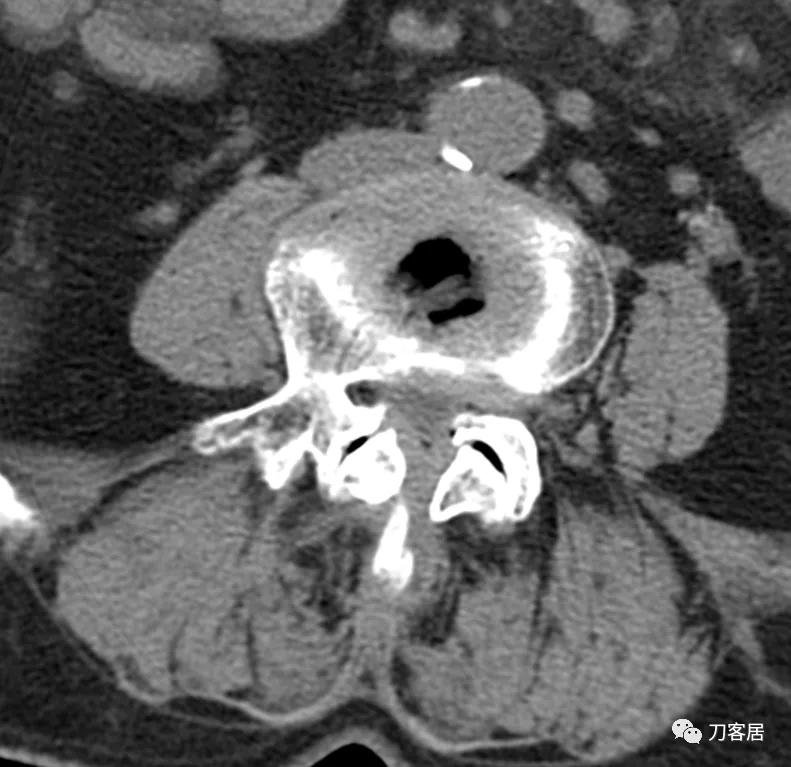

患者为69岁,女性, 就诊日期:2021年11月8日。因晨起腰痛2天,就诊当日有缓解。疼痛自腰部放射至大腿后侧。2004-2005年曾有腰椎骨折病史,保守治疗后愈。

腰椎X线片提示腰5峡部裂,腰5椎体前滑脱1度,膝关节X线片提示退变增生,右侧髌股关节增生、狭窄、骨刺形成。骨密度提示骨质疏松,T值最低-3.3。2014年曾换心脏瓣膜手术,长期服用华法林,辅酶Q10, 盐酸曲美他嗪。

诊断:骨质疏松症,腰5峡部裂,腰5椎体前滑脱1度,双膝关节创伤性关节炎。